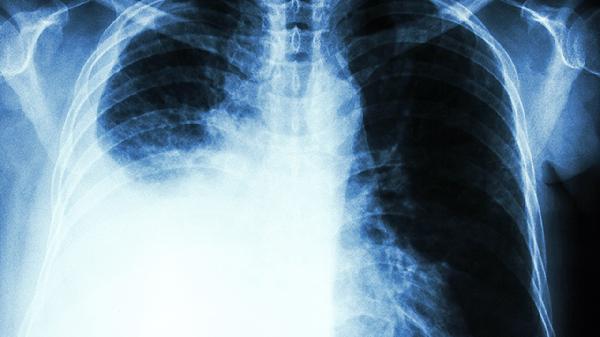

3、运动时不注意空气质量

晨跑时汽车尾气浓度最高,公园里花粉季的PM2.5可能超标。建议出门前查看空气质量指数,污染严重时改为室内运动。